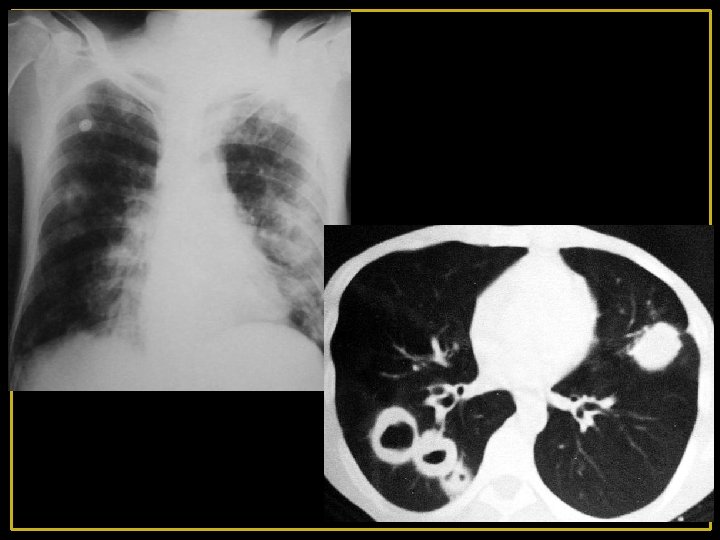

Aspergillome - Amas mycéliens enchevêtrés - Il se développe dans une cavité préexistante chronique (++ séquelle de tuberculose) - Cavité contenant une masse arrondie ou ovalaire, bien limitée, dense et homogène, déclive et mobile, pouvant contenir des calcifications Bénignes - Lorsque la masse mycélienne est volumineuse, l'air intracavitaire se réduit à un croissant gazeux supérieur